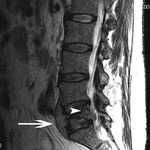

Ressonância nuclear magnética da osteomielite: o espaço do disco T11-T12 é envolvido com discite (A). Existe um comprometimento ósseo de ambas as vértebras indicado pelo sinal T2 elevado dos corpos vertebrais. A seta indica um disco intervertebral normal saudável

Cortesia do Dr K. Singh; usado com permissão